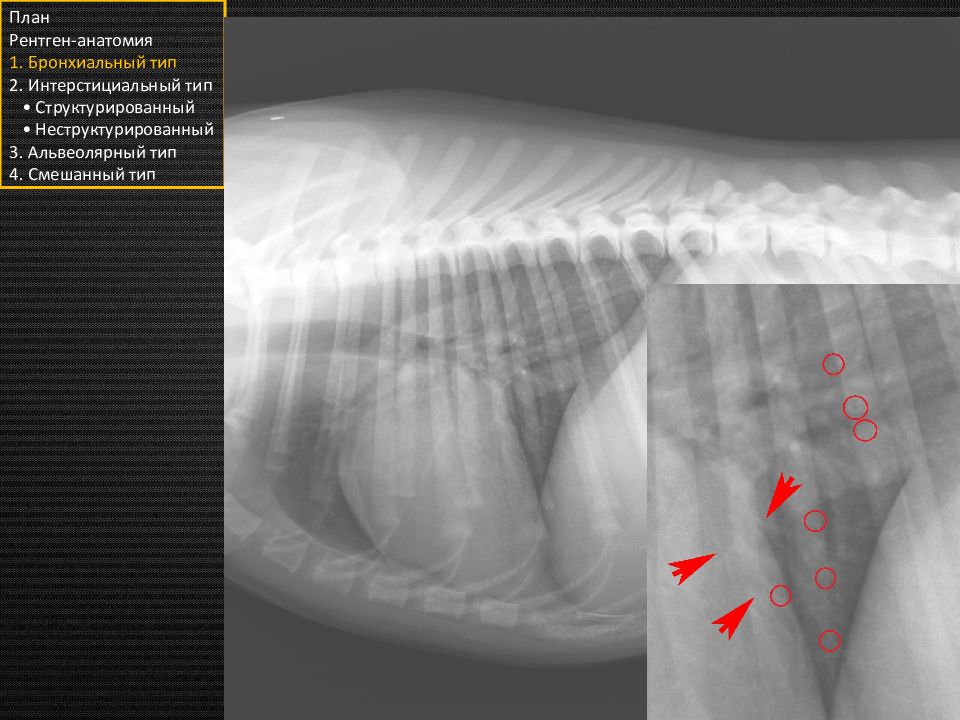

Чётко очерченные очаговые затемнения на фоне лёгких. Возникают при ограниченных изменениях в интерстиции лёгких. План Рентген-анатомия 1. Бронхиальный тип 2. Интерстициальный тип • Структурированный • Неструктурированный 3. Альвеолярный тип 4. Смешанный тип